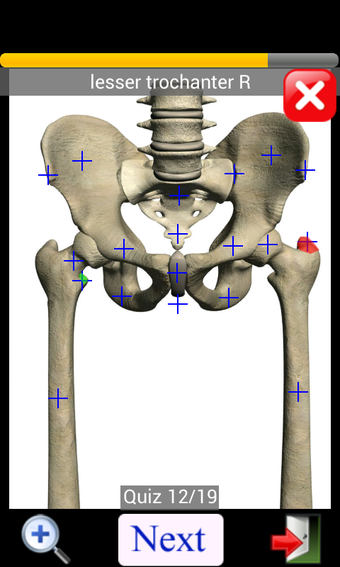

Anatomy Quiz Free es una aplicación de Android de Education Mobile que ofrece una amplia gama de cuestionarios para ayudar a los usuarios a aprender anatomía humana. La aplicación cuenta con más de 500 cuestionarios que ponen a prueba tu capacidad para identificar la ubicación correcta de un objeto dado su nombre. Los cuestionarios se generan a partir de modelos de anatomía 3D virtuales, lo que los hace más atractivos e interactivos. La aplicación es gratuita y no hay versiones premium ni compras dentro de la aplicación.

La aplicación es compatible con los idiomas inglés, francés, español y alemán, lo que la hace accesible para usuarios de diferentes partes del mundo. Las imágenes de alta resolución son nítidas y claras, y la función de zoom con pellizco te permite acercar y alejar las imágenes para una mejor vista. El cuestionario de posición viene con un temporizador, lo que lo hace más desafiante y emocionante. Además, la aplicación tiene una función de transferencia a la tarjeta SD, lo que facilita su transferencia a otros dispositivos.